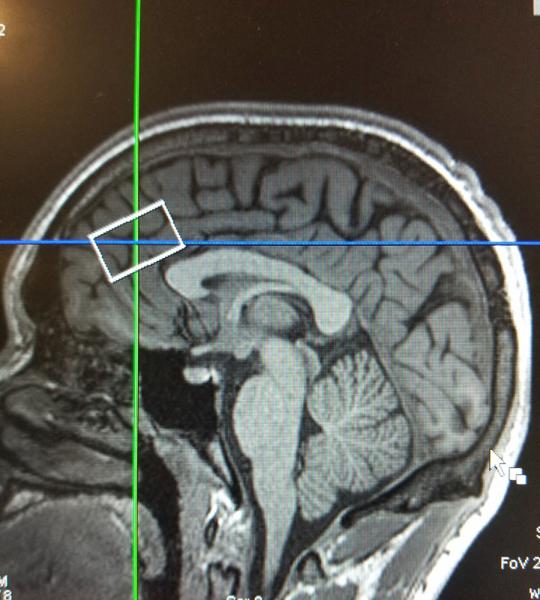

The sagittal slice of the brain looking specifically at the anterior cingulate cortex (ACC). The white box is representing the coverage of the ACC.

The preclinical data, by providing evidence that clavulanic acid might be repurposed to treat cocaine use disorder, laid the basis for the clinical study in human patients that will be funded by the new NIDA award. The clinical study will involve the use of functional magnetic resonance imaging (fMRI) to examine the brain in persons with recent cocaine addiction. “Spectroscopy will allow us to observe changes in glutamate levels in the brain, and adding fMRI will enable us to look at associated changes in cocaine craving,” Dr. Morrison said.